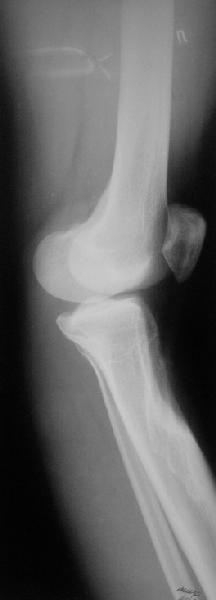

Коллеги из детского отделения направили 18-летнюю студентку с варусно-рекурвационной деформацией проксимального отдела голени.

Жалобы у нее на появившиеся боли в колене при нагрузках. Признаков воспаления не было и нет, опухолевого роста также. Природа дефекта в области бугристости не очень понятна. Дополнительно сделали КТ и боковой снимок в максимальном разгибании - все в приложении.

По-поводу деформации - Вы имеете дело с епи-метафизарной деформацией, скорее всего по причине преждевременного частичного закратия проксимальной зоныы роста большеберцовой кости.

Рекурвации в коленном суставе нет, есть рекурвационная деформация проксимальной части голени.

За точку отсчёта при планировании коррекции надо взять латеральный снимок в максимальном стрессе на разгибание. Остеотомию необходимо произвести тот час дистальнее места прикрепления собственной связки надколенника.(очень важно)

Ориентировачно на боковой проекции угол между тибиальным плато и анатомической осью тибии на передне-боковой проэкции должен быть порядка 90 градусов, а на боковой 80, кроме того на боковой проэкции при выпрямленном колене передний кортекс большеберцовой кости должен находиться на одной линии с передним кортексом бедренной кости.